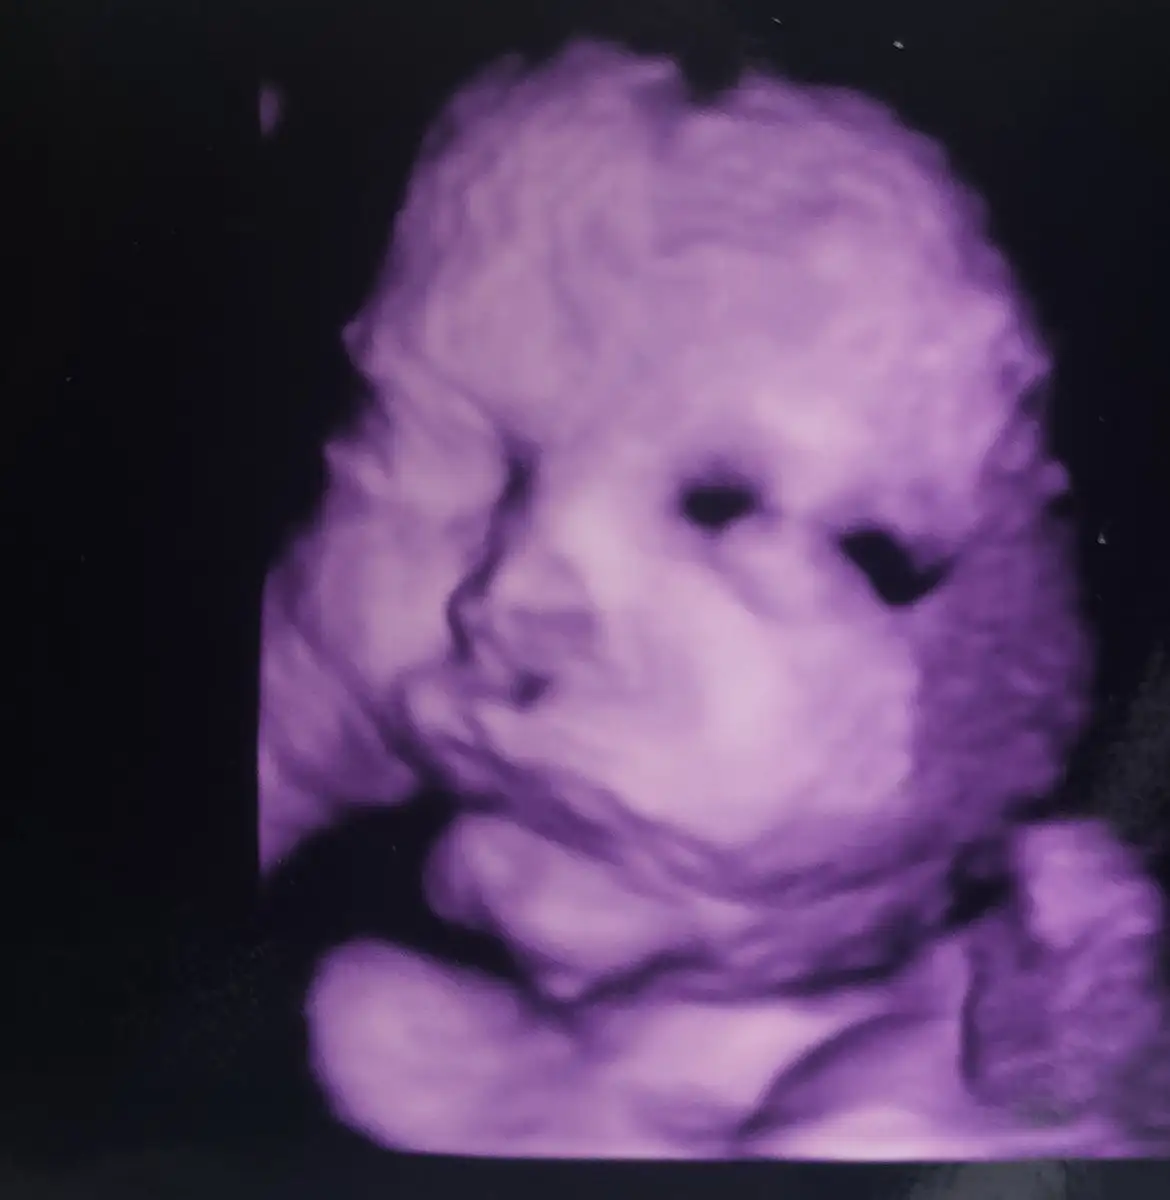

Kızlar doktorum şehir dışındaydı ve başka doktora çalışabilir raporu almaya gittim. Gittiğim doktor şehrimizin bilinen bir doktoruydu ve inanılmaz ilgili biz sormadan her şeyi açıklayıcı konuşuyordu. Hatta girdiğimde direkt söylediği şey şuydu “senin doğumunu burda yaptırıyoruz” beni hemen sahiplenmesi hoşuma gitti açıkcası. Eşim önceki doktor u pek sevmiyordu çok konuşmadığı için. Bana aylardır işkence çektirdiniz bak bu doktor herşeyi söyledi dedi. %99 hastanemi ve doktorumu değiştirdim diyebilirim. Gelişimi çok iyi 38. Haftada almamız lazım dedi. 3 ocak gibi olur dedi ama eşim daha geç tarih istedi doktorda olur dedi. 2300 gram olmuş. Cihazları superdi ilk kez cocuğumun yüzünü gördüm doğru düzgün :işsiz: Fiyat olarak doktorla konuşmadık ama sekreteri 1500 dedi. Bazı hastaneler spinal, estetik dikiş vs gibi ayrıntılara extra ücret alıyor bunda durum ne bilmiyorum 15 aralıkta gittiğimde konuşacağım. Diğer hastanede personel yakını olduğum için fiyatları çok umursamamıştım bunda durum nedir bilmiyorum. Odalar nasıl vs bu soru işaretlerimiz biterse bu doktorla doğuma gireceğim :) Bu arada dün ki sancılarım şuan yok. Gece aşağıdaydı sabah yukarı çıktı. Doktorda erken doğum riski görmedi

ay minişşş maşallah coktatlı yerimonu mor ayarlamıslar ısıgı cok tatlışş ya çok sevindim dr.a ısınmanıza çok da güzel ilgilenmiş odana as canım ben de asacagım kolaj yapıp resımlerı cokguzel.bır hatıra olur bebegıne ❤ siz karar verdiniz mi ve hastane yakınlıgı nedir size